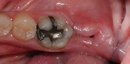

Diş ekimi, kaybedilen dişlerin yerine yapay dişlerin yerleştirilmesi işlemidir. Bu işlem, hem estetik hem de fonksiyonel açıdan birçok avantaj sunmaktadır. Diş ekimi, günümüzde diş hekimliği alanında en yaygın kullanılan yöntemlerden biri haline gelmiştir. Bu makalede, diş ekiminin faydaları detaylı bir şekilde ele alınacaktır. Diş Ekimi Nedir?Diş ekimi, kaybedilen dişlerin yerine cerrahi bir işlemle titanyum veya benzeri malzemelerden yapılan yapay diş köklerinin yerleştirilmesini içeren bir tedavi yöntemidir. Bu işlem, diş kaybının neden olduğu estetik kaygıları gidermenin yanı sıra, çiğneme fonksiyonunu da yeniden kazandırmaktadır. Diş Ekiminin Estetik FaydalarıDiş ekimi, hastaların gülümseme estetiğini önemli ölçüde iyileştirmektedir. Aşağıdaki avantajlar estetik açıdan dikkate değerdir:

Diş Ekiminin Fonksiyonel FaydalarıDiş ekiminin fonksiyonel avantajları da oldukça önemlidir. Bu avantajlar şunlardır:

Diş Ekimi SüreciDiş ekimi süreci, genellikle birkaç aşamadan oluşur: